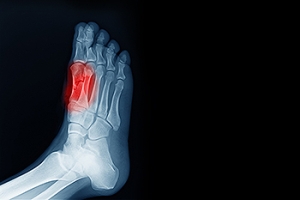

If you suspect that you have flat feet, it is best to consult your podiatrist. Your foot doctor will examine the suspected foot and observe how it looks while you sit and stand. He or she may take an X-ray to determine how serious the condition is. Some common signs of flatfoot include toe drift, in which the toes and front part of the foot point outward, a short Achilles tendon, and a heel that tilts outwardly while the ankle tilts inward.

Ankle Fracture? Don’t Wait for Treatment